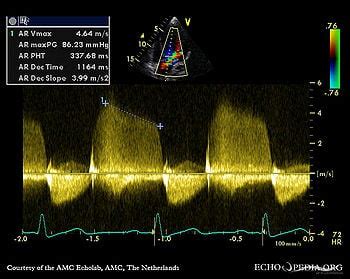

Case 163 - Echopedia

Case 163 - Echopedia www.echopedia.org

aortic regurgitation severe doppler continuous wave signal case bicuspid valve file